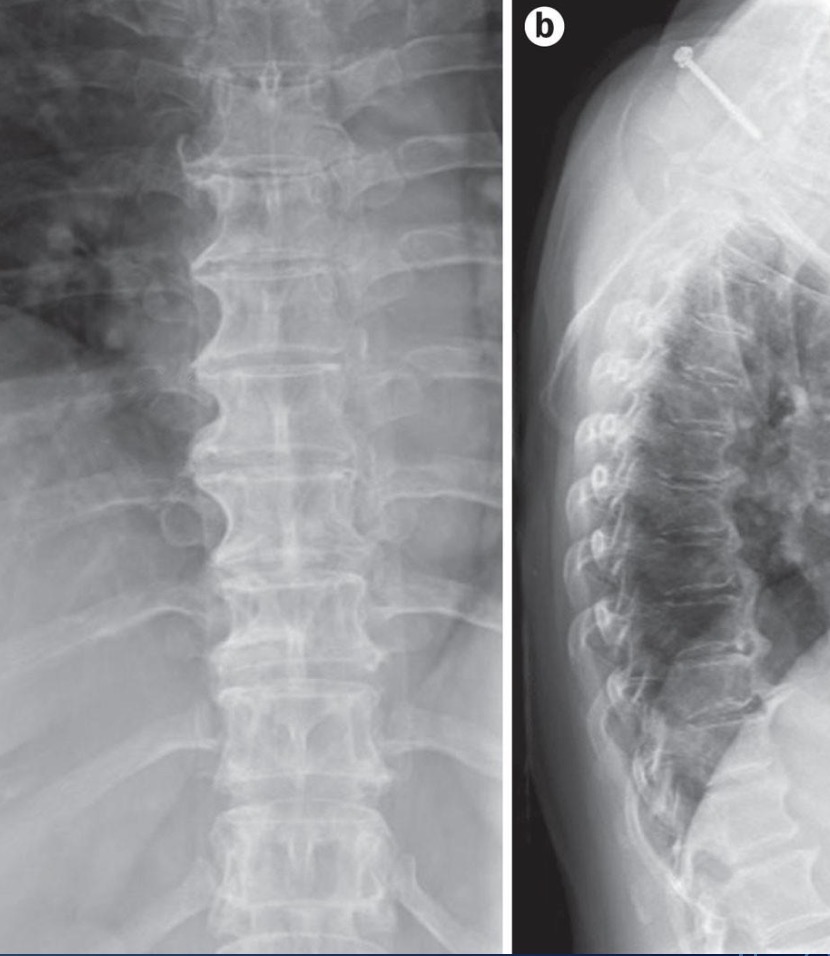

Diffuse Idiopathic Skeletal Hyperostosis ( DISH ) ⭐

Flowing, bridging osteophytes - typically anterior + right side

Requires 4 or more connecting vertebrae